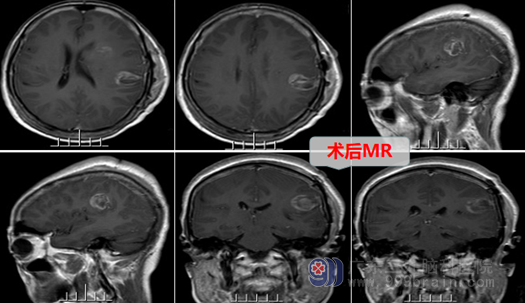

入院后,欧阳辉主任组织外十科团队尽快给陈姐完善了各项术前检查和准备工作,我院MR示:左侧额顶叶占位病变:高级别胶质瘤可能性大。欧阳主任团队于2022年10月17日为陈姐进行了“左侧额顶叶胶质瘤切除术”,术中冰冻病理及后期常规病理报告证实为:高级别胶质瘤。术后患者神志清醒,回答正确,四肢活动都是很好的,也没有出现其他并发症。

陈姐的家人照顾着她,眼看着陈姐的身体一天天的恢复的越来越好,一家非常满意手术效果,但医生告诉她:高级别胶质瘤术后还需要放疗、化疗等综合治疗,才能巩固疗效并防止复发。